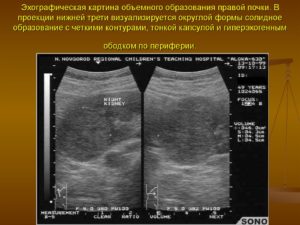

Объемные образования почек